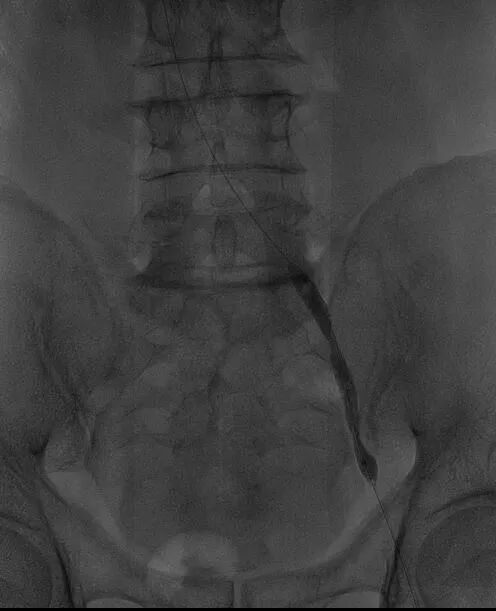

经过全面评估和术前准备,团队为李叔叔制定了“左下肢髂静脉造影+髂静脉球囊扩张成形术”的个性化手术方案。

手术过程中,田轩团队凭借精湛的介入技术,经大隐静脉入路穿刺,成功开通闭塞的髂静脉。

术中造影进一步确认,李叔叔左下肢深静脉全程闭塞,血流无法正常回流。